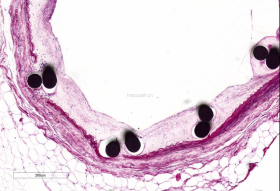

使用德国EXAKT切磨系统进行硬组织切片,特别是对于含有金属这类植入物的组织,是一种精确的组织切片技术。

各类尺寸的含金属植入物骨、牙齿、血管等硬组织样本脱水,7200树脂浸润包埋,后期用标准尺寸(25mm*75mm)的树脂片进行切磨片处理。

将包埋好的硬组织树脂块,用EXAKT 硬组织切片机先切一个200um的厚片,然后再通过EXAKT 硬组织磨片机将其磨到20-30um薄片,样本是已经硬组织包埋好的含金属的动物样本。

具体步骤:包埋块修开切面抛光-平行粘片装置粘片-硬组织切片机切片-硬组织磨片机磨片抛光成片。

针对不同的病理阅片指标需求,行HE染色、Masson染色、亚甲基蓝-酸性品红染色、VG染色、Movat染色等。